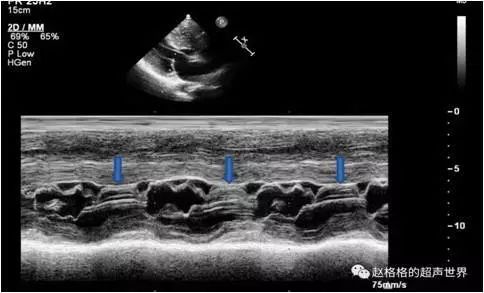

4.超声心动图检查

显示左心室壁显著增厚,心室间隔较心室后壁更为肥厚,左心室腔小,流出道狭窄和心脏收缩时二尖瓣前瓣叶向前移位(SAM征)。

超声心动图

SAM征小知识